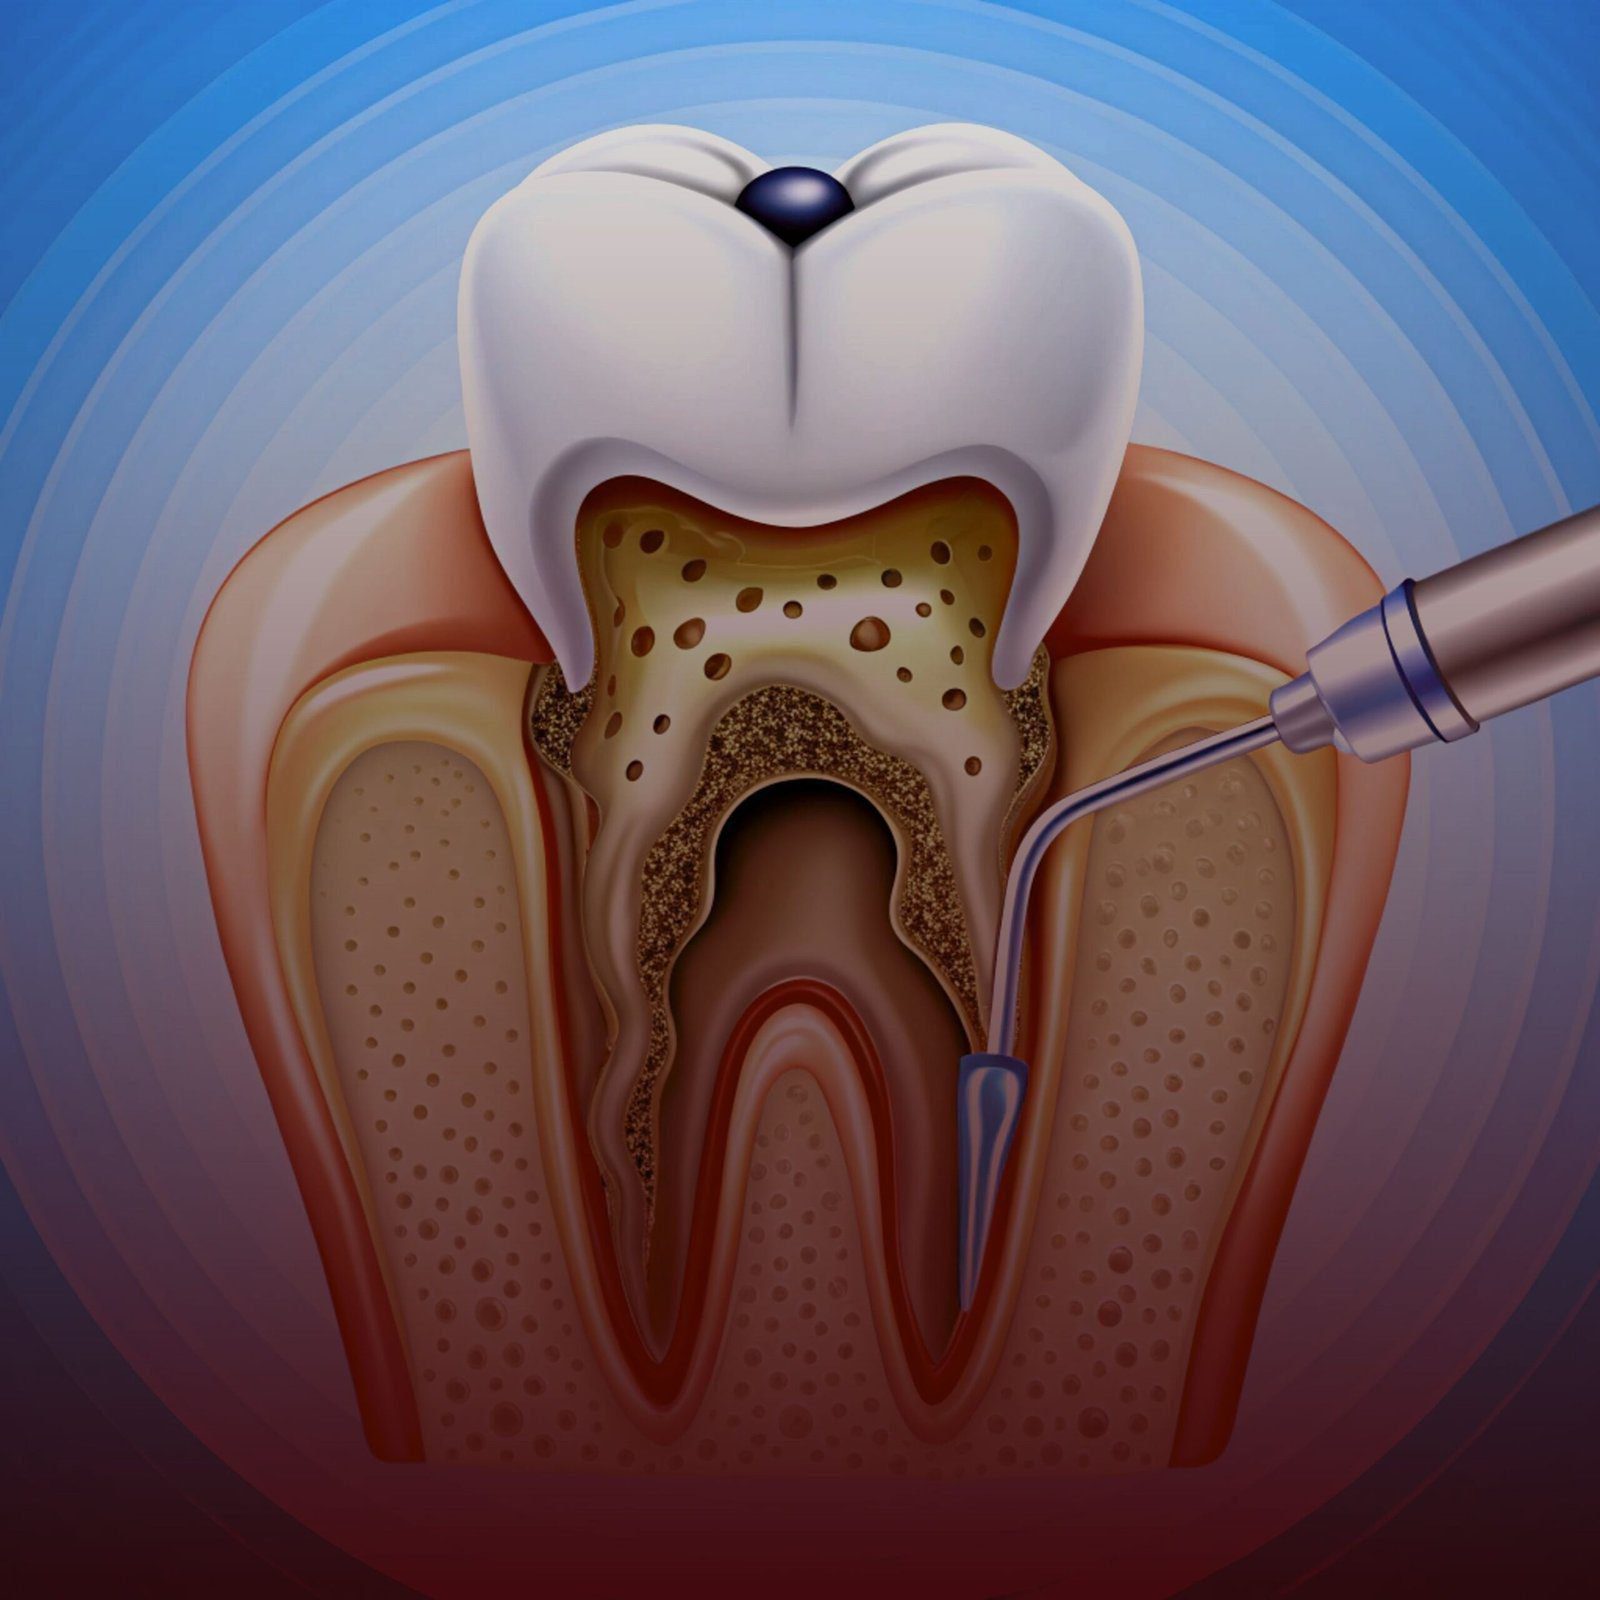

علاج جذور الأسنان في تركيا

أفضل عيادة لعلاج جذور الأسنان في تركيا – إسطنبول

استئصال ذروة الجذر | علاج جذور جراحي

علاج خراج الأسنان في تركيا